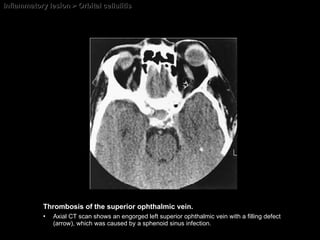

Inflammatory lesion > Orbital cellulitis Thrombosis of the superior ophthalmic vein.   Axial CT scan shows an engorged left superior ophthalmic vein with a filling defect (arrow), which was caused by a sphenoid sinus infection.